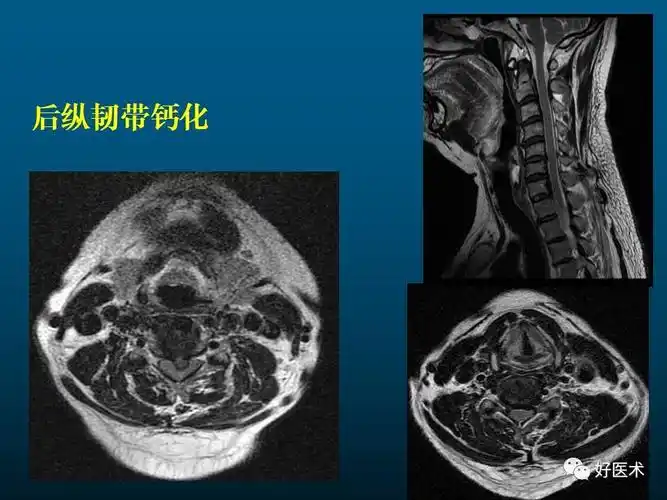

颈椎间盘突出征核磁共振矢状位(mri)